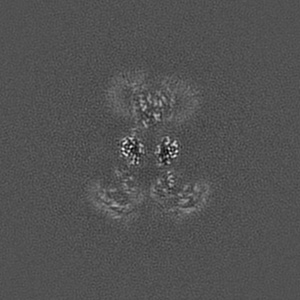

Glycine and glutamate bound GluN1a-GluN2B NMDA receptors in non-active 1 conformation at 2.97 Angstrom resolution

Structural insights into binding of therapeutic channel blockers in NMDA receptors.

Chou TH , Epstein M, Michalski K, Fine E, Biggin PC , Furukawa H

(2022) Nat Struct Mol Biol , 29 , 507 - 518